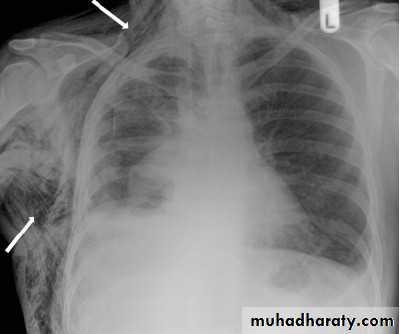

Surgical emphysema may complicate PNX when air escape to subcutaneous tissuesDiseases of the Pleura Dr.Mustafa Nema. Baghdad College of Medicine 2013